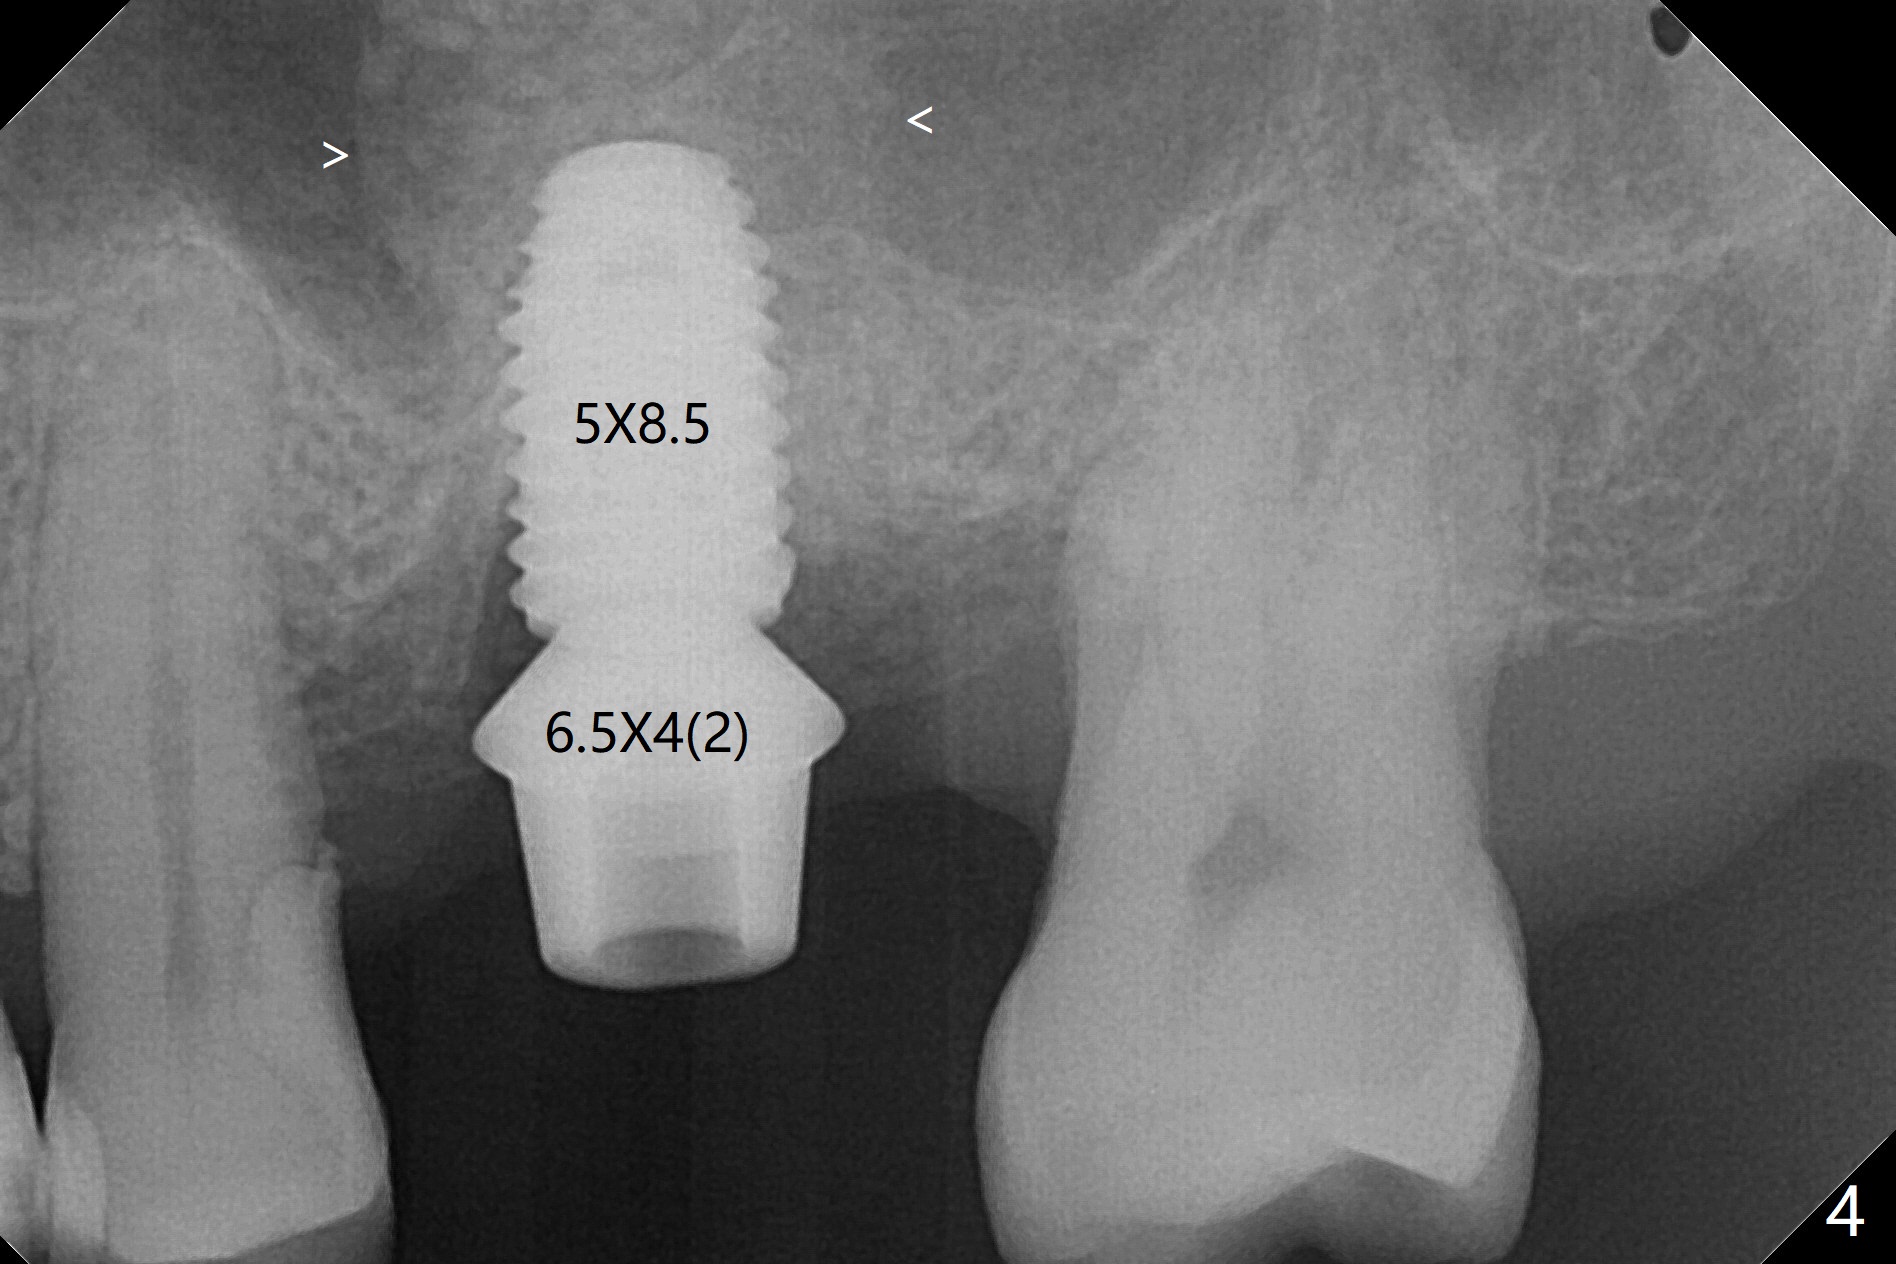

72岁男14号牙腭侧根尖接近上颌窦(图一,二:P),牙齿拔除后,根尖对刮治敏感,冲洗后,开始导板钻洞,圆钻穿透窦底,放置粘性骨粉和报废植体提升(图三:箭头)。放置小张PRF和骨粉(图四:箭头),植入正式植体,基台和骨粉(图五:*),最后覆盖PRF(图六),为了防止骨粉从邻牙牙龈沟(>)丢失,覆盖树脂敷料。基台和前后邻牙使树脂敷料术后一周巍然不动(图七:A)。术后一个月撤除树脂敷料,牙槽窝已经愈合(图八)。再过两周牙槽窝上皮好像进一步成熟(图九),然后塞入一个龈线,制备临时牙冠。